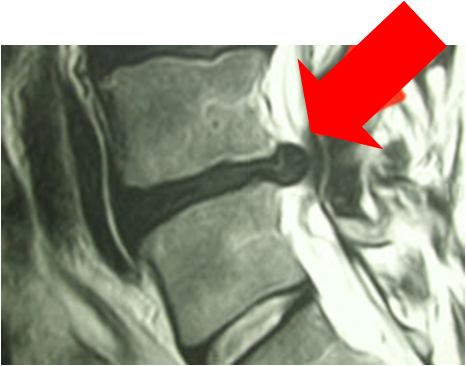

ΜαγνιτικÞ τομογραφßα πριν και μετα απü την επÝμβαση